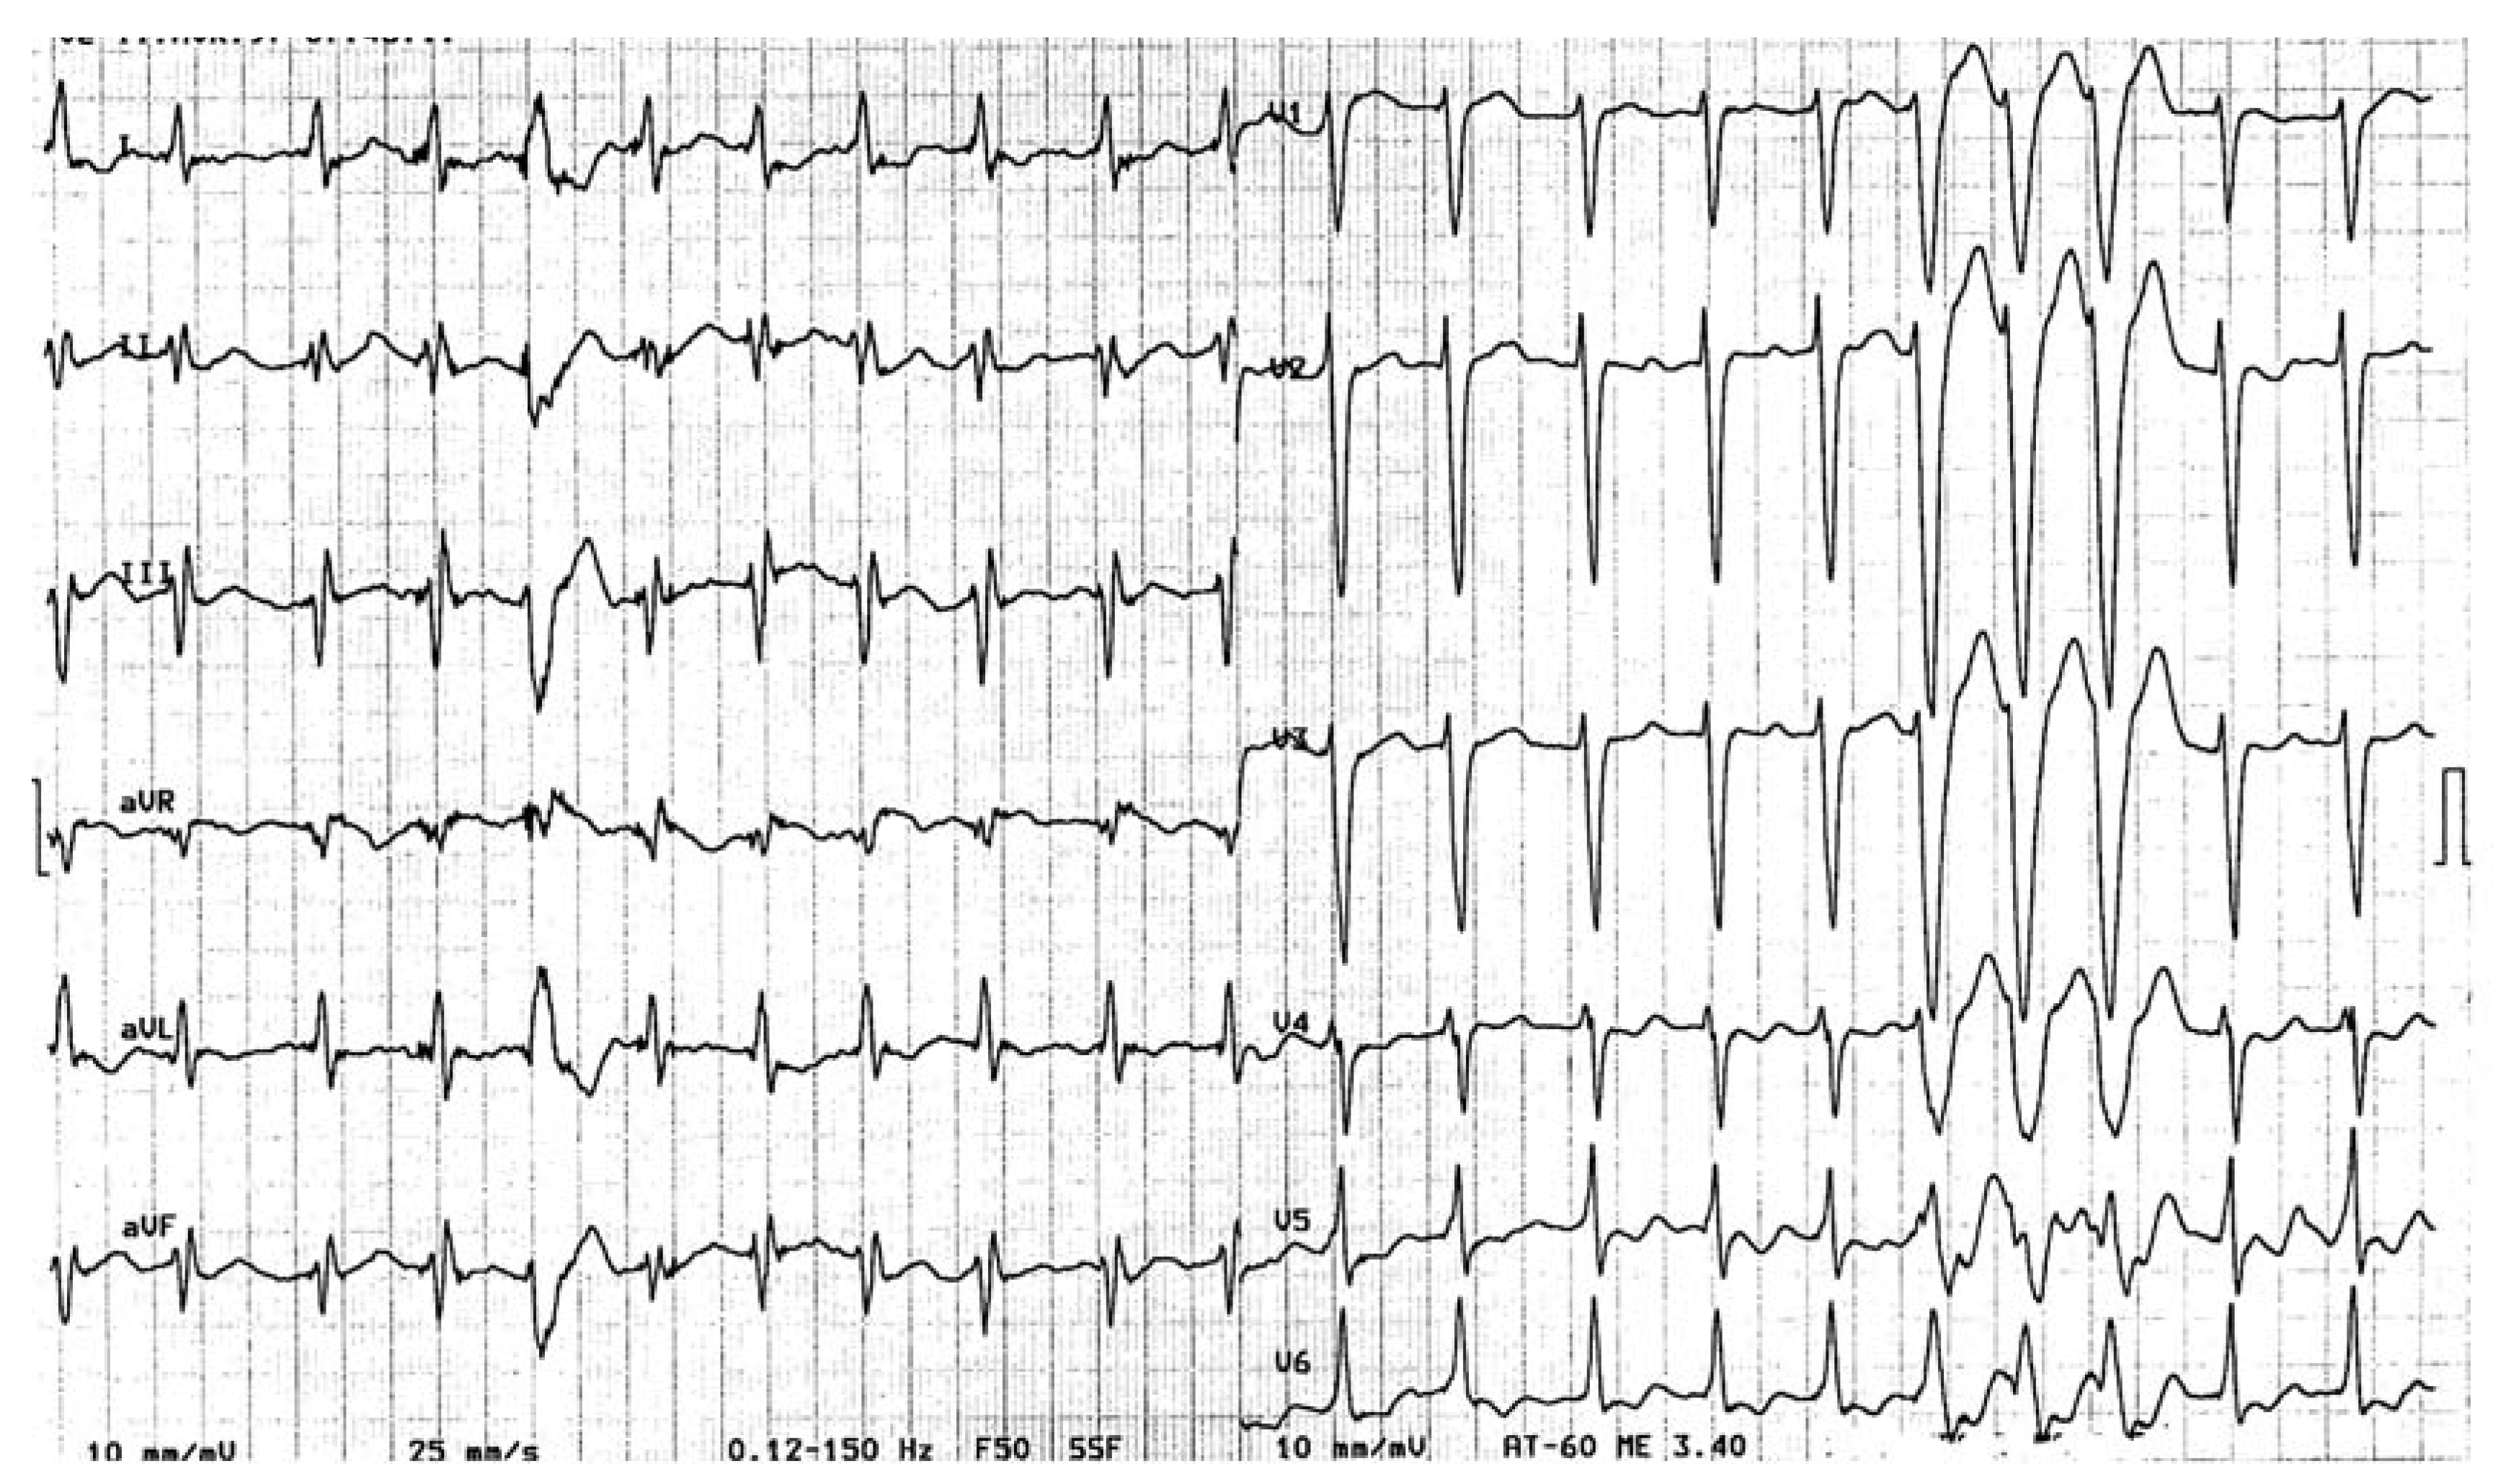

Tachycardie Ventriculaire?